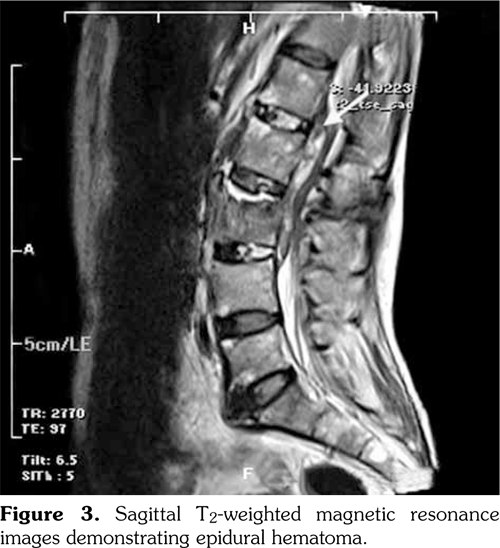

Laboratory assessment before the surgery demonstrated the erythrocyte sedimentation rate as 55 mm/h and C-reactive protein as 43.7 mg/L. Hepatitis markers and Brucella agglutination test were negative. The lumbosacral MRI which was performed before the surgery detected edema at the L3 vertebral corpus, oblique fracture at the L3 vertebral corpus, and 75¥13 mm epidural hematoma through the L1-L3 vertebrae (Figure 3, 4). After the epidural hematoma drainage and decompression surgery, the patient was transferred to the physical medicine and rehabilitation inpatient clinic for the rehabilitation program.